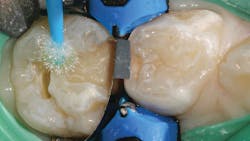

Once preparation and removal of the infected dentin is achieved, a sectional matrix and ring system (Composi-Tight 3D XR, Garrison Dental Solutions) is used. Taking particular care at the gingival margin, proper matrix placement will ensure control over leakage and any possible contamination, which is important for long-term success (figure 2).